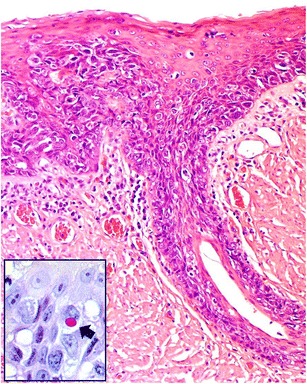

Fig. 1.

Biopsy from right piriform fossa of the hypopharynx shows grade 3, poorly differentiated carcinoma (a) which is positive for CK7 (b). There is pagetoid spread in the overlying squamous epithelium (c). The Paget’s cells are also positive for CK7 (d). Insert: alcian blue diastase-PAS highlights the cytoplasmic mucin within the carcinoma cells